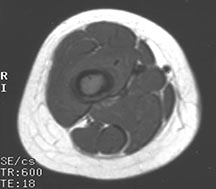

- May arise from any bone and any site within a bone (epiphyseal, metaphyseal, diaphyseal)

- Radiographically variable appearance: may appear benign (geographic) or malignant (permeative or moth eaten)

- Pain and soft tissue swelling